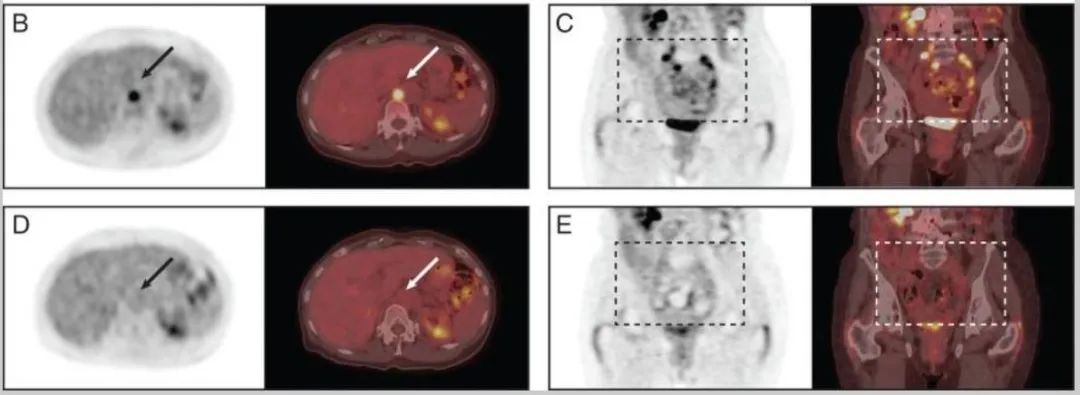

一名65岁男性酒精性肝硬化 , 被诊断有多发性肝细胞癌(HCC) 。 患者被评估为不能手术 , 不适合进行TACE或全身化疗 。

在讨论了治疗方案后 , 患者决定接受低剂量沙利度胺(每天100mg)治疗 。 在获得书面知情同意后 , 他同意每日两次接受沙利度胺50mg , 并在门诊进行随访 。

沙利度胺治疗三周后 , 他偶尔自诉有皮疹和瘙痒 。 幸运的是 , 后续的肝脏生化检查、血清胎蛋白水平和动态计算机断层扫描显示 , 沙利度胺治疗4.5个月后 , HCC完全缓解 。